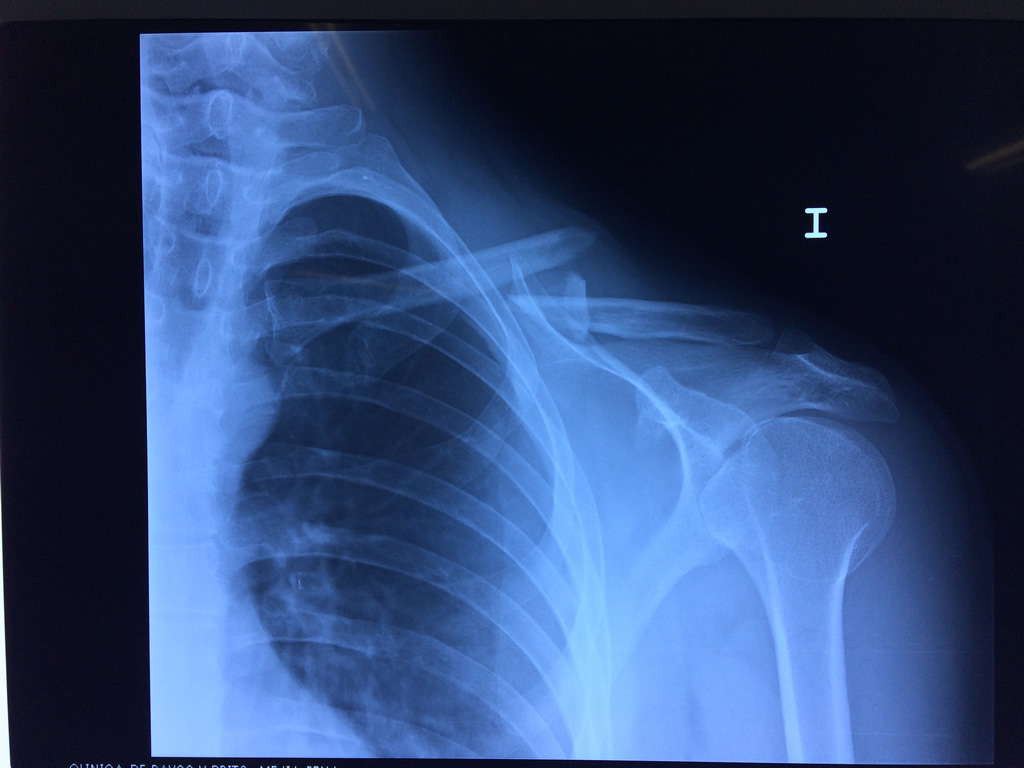

Fémur - Clavícula

La clavícula es un hueso largo, con forma de "S" itálica, situado en la parte anterosuperior del tórax. Junto con la escápula forman la cintura escapular. Se puede palpar por toda su longitud y se extiende del esternón al acromion de la escápula, siguiendo una dirección oblicua lateral y posterior.